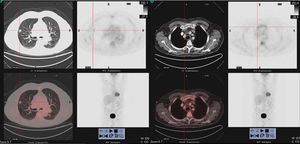

18F-FDG PET/CT scan images showing (on the left) a solid spiculated hypermetabolic nodule (SUVmax7.5), in punctiform contact with the pleura and the fissure, measuring about 14mm, located in the anterior segment of the right upper lobe. Hypermetabolic bone lesion (on the right) with lytic component at the distal end of the right clavicle (SUVmax 8.4).

We report the case of 77-year-old man, former smoker with a cumulative index of 50 pack-years, history of dyslipidemia, IgG lambda monoclonal gammopathy of uncertain significance (MGUS) (monoclonal component [MC]: 4.8g/l) diagnosed in 2014, stable, with no evidence of progression, monitored annually by hematology, and moderate COPD, non-frequent exacerbator phenotype, receiving bronchodilator therapy, with mMRC dyspnea grade 1, and no previous admission due to exacerbation, and no respiratory symptoms or accompanying constitutional syndrome. In November 2017, after a routine chest X-ray revealed a solitary pulmonary nodule, a computed tomography (CT) scan of the chest was performed that showed a spiculated nodule measuring 13mm in the anterior segment of right upper lobe (Fig. 1), in contact with the pleura, and with retraction of the adjacent horizontal fissure. Laboratory blood tests (biochemistry, including total proteins, immunoglobulins, serum proteins, free light chain index, complete blood count, and coagulation) were normal. A positron emission tomography (18F-FDG-PET/CT) showed a solid hypermetabolic nodule (spiculated SUVmax 7.5) measuring 14mm in punctiform contact with the pleura and fissure, suggestive of primary neoplastic etiology (Fig. 1). Multiple hypermetabolic bone lesions of lytic component were observed at the distal end of the right clavicle (SUVmax 8.4) (Fig. 1) and in the D3 vertebral body, and lesions with a blastic appearance were seen in the left femoral head/neck union (SUVmax 12). These lesions were initially thought to have a metastatic origin. Moreover, an irregular tracer distribution was described in other bony structures that could not be attributed to morphological lesions, and discrete metabolic activity was detected in the sternal manubrium, so a secondary etiology could not be ruled out. A CT-guided transthoracic biopsy of the lung lesion was then performed, which was positive for adenocarcinoma of pulmonary origin. To complete staging (T1BN0Mx), we decided to obtain a biopsy of the lytic lesion in the right clavicle. This was positive for plasma cell cancer, consistent with plasmacytoma/multiple myeloma (MM).